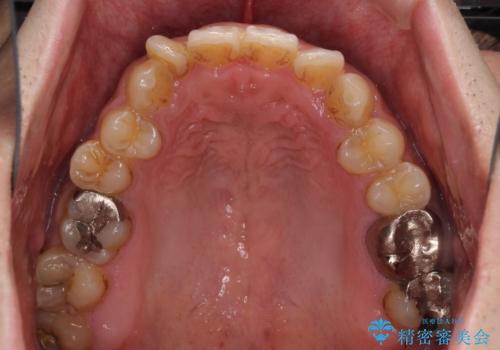

- 前歯のデコボコを気にして来院された患者様です。

前歯が90度近く捻れていたため、しっかりと治すことを考えるとワイヤー矯正の方がおすすめではありましたが、本人の希望によりインビザラインを用いて矯正治療を行うこととしました。

インビザラインは、十分な装着時間が達成されると前歯のデコボコをしっかりと改善できますが、1日の装着時間が20時間に達しなくなると、不十分な仕上がりとなるため、しっかりと装着するよう指示をしました。

途中2年強の来院がなく、改善されていたデコボコが元に戻ったり、装着時間が不足しており前歯のデコボコは十分に改善することはできませんでしたが、5年間の有効期限内で可能な限り歯列を整えることができました。